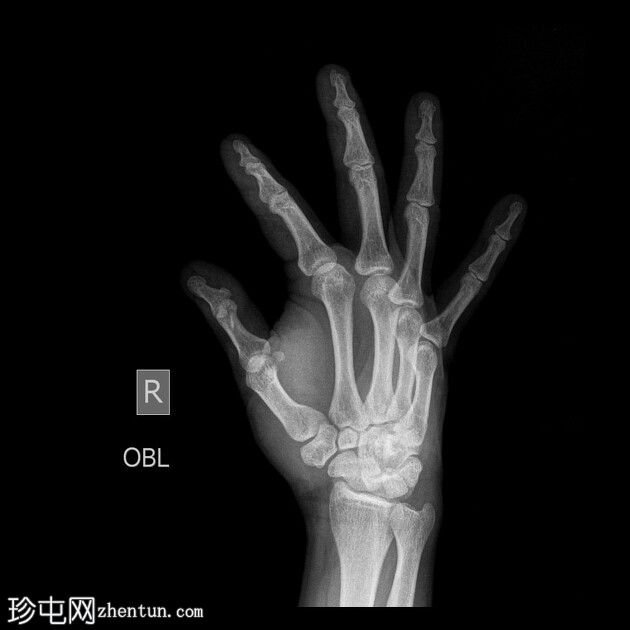

患者一天前因40公斤重的沙井事故,右手食指和中指遭受挤压伤。

X光片

斜位

右手X光片显示中指远端指骨末端失去正常的光滑轮廓,皮质轮廓不规则,提示远端骨折畸形。骨折在斜位片上更容易被看到,并伴有轻度移位和周围软组织肿胀。

X光片结果显示中指远端指骨末端骨折,皮质轮廓不规则,正常轮廓丧失,可能由直接创伤引起,例如重物撞击或挤压伤。